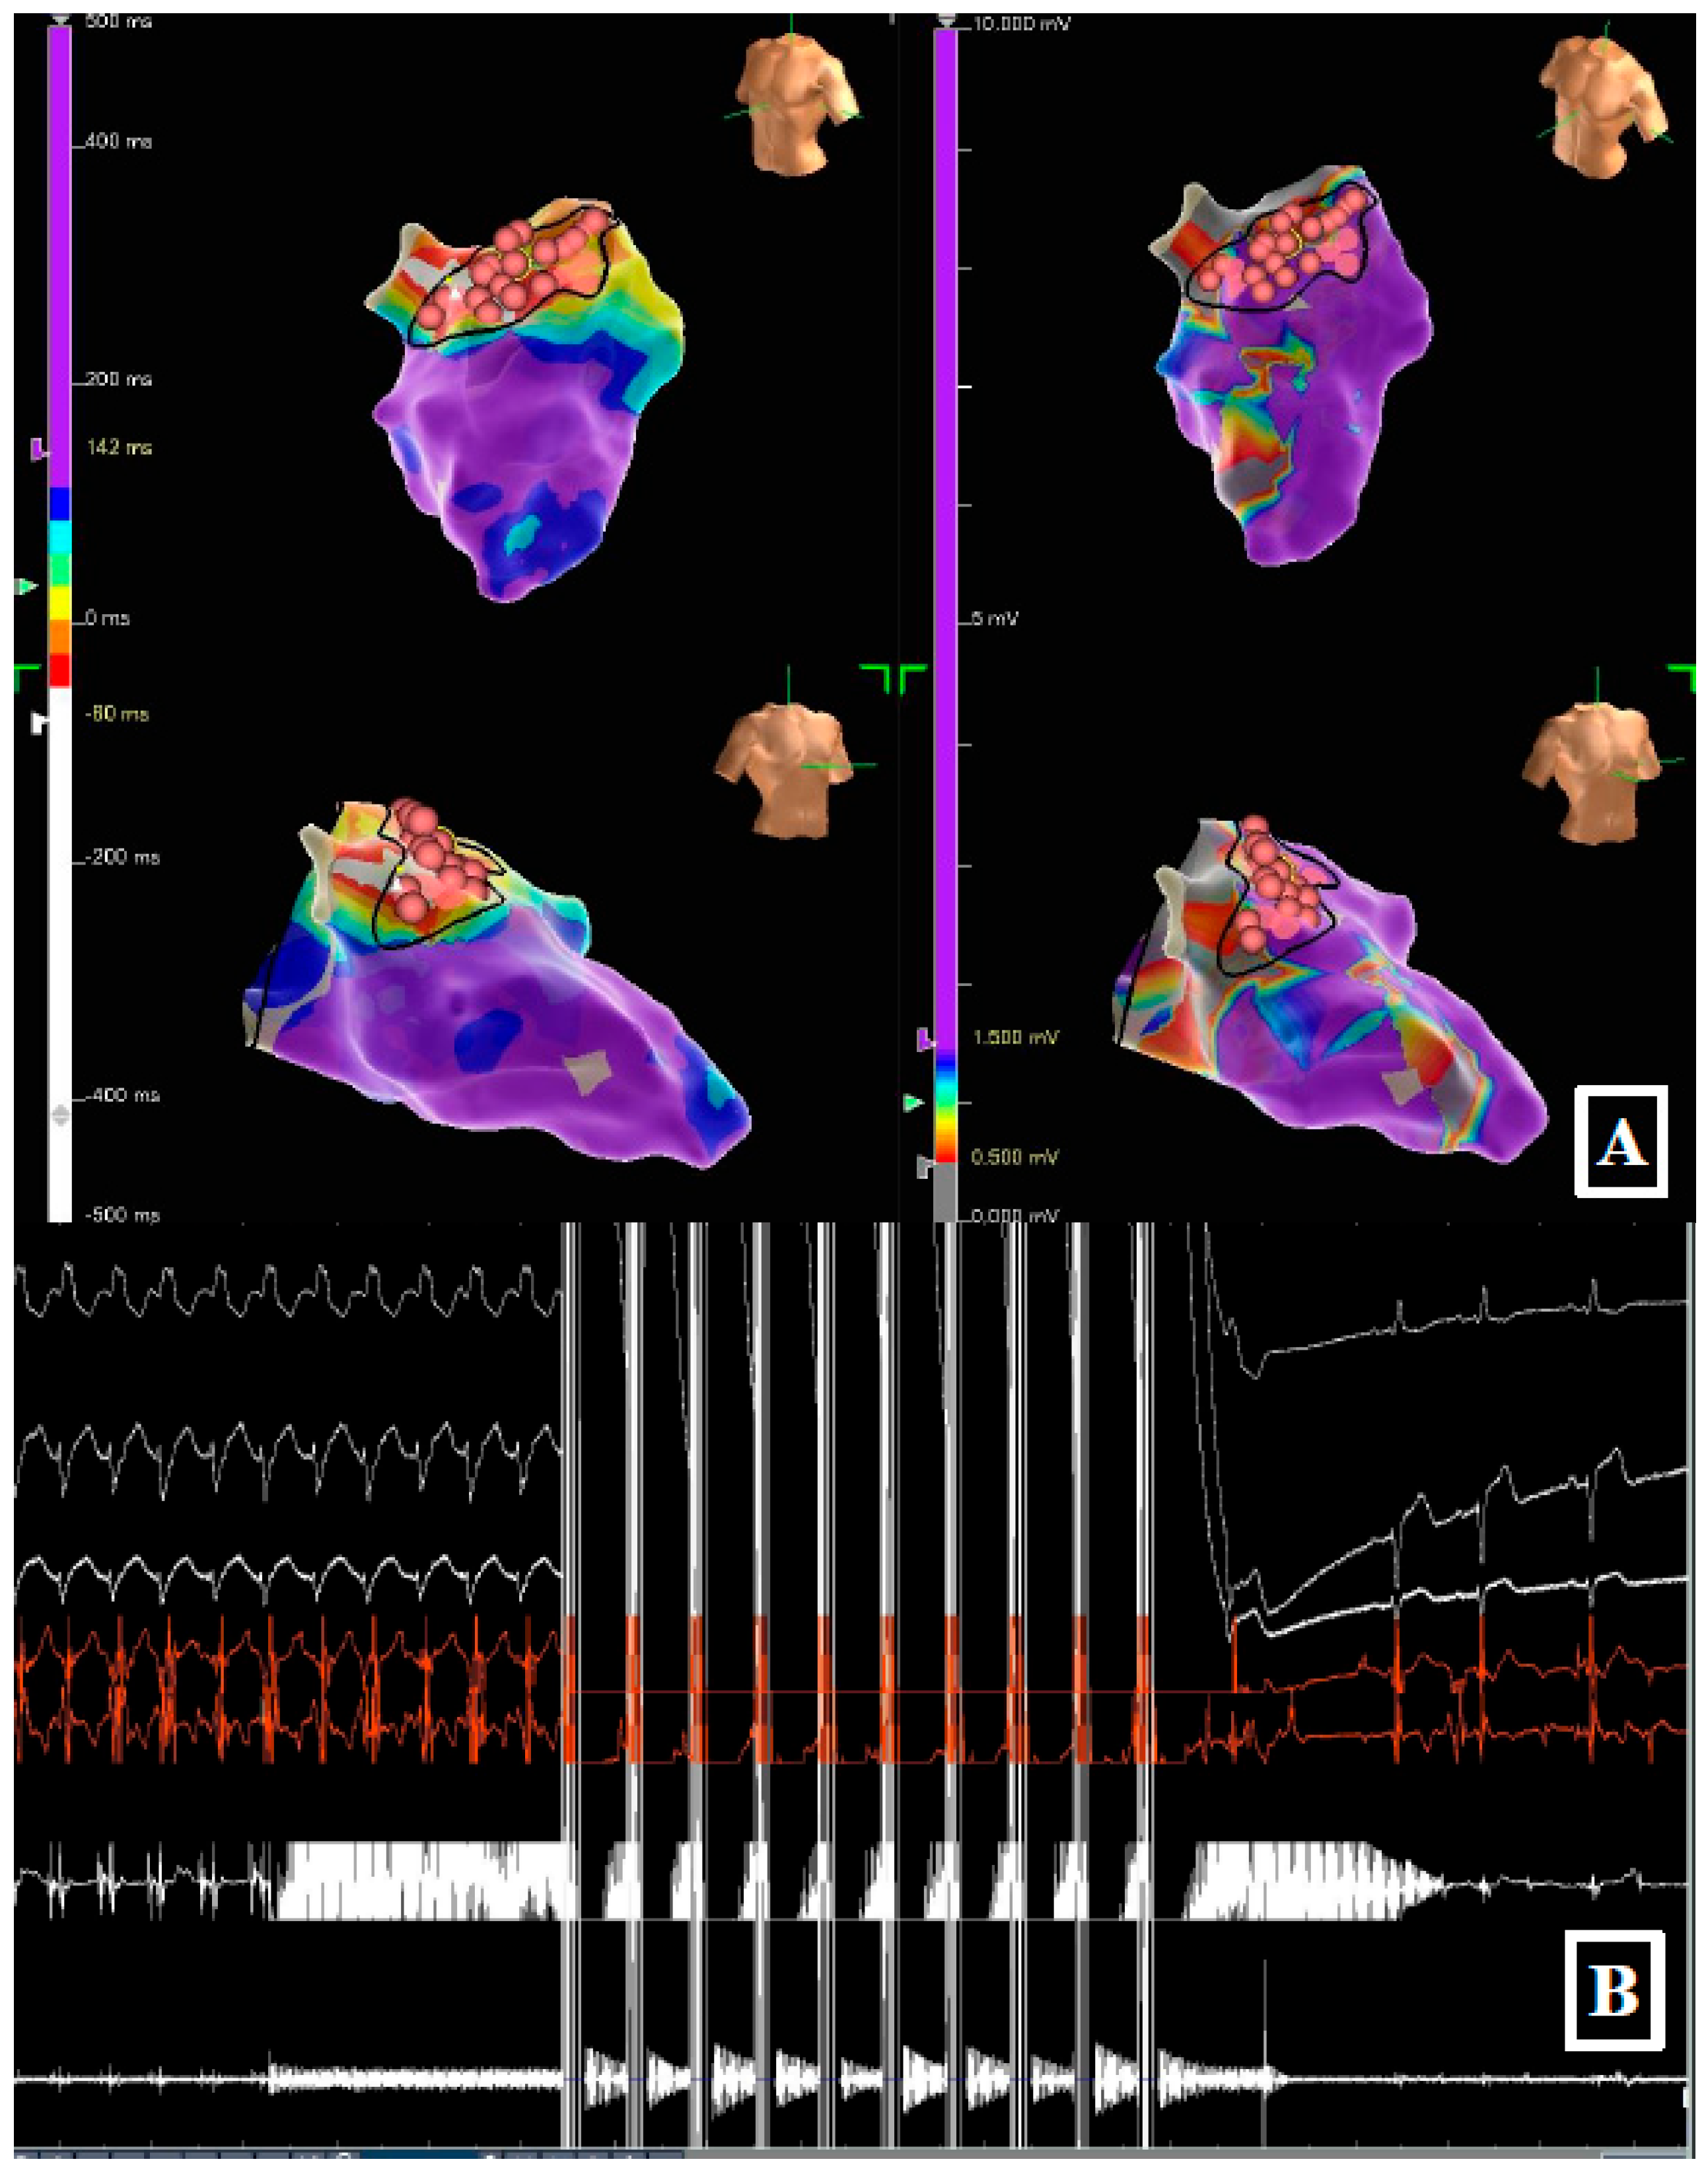

A 71-year-old male with ischemic cardiopathy (LVEF 30%), prior coronary bypass grafting and previous ventricular septal defect repair with a Dacron patch, was admitted for recurrent monomorphic VT treated by multiple ICD shocks. The clinical VT (RBBB morphology) was inducible at baseline (Figure 2). Mapping revealed a complex heterogeneous substrate with areas of slow conduction in the antero-septal LV. Due to the thickness of the septum and the presence of surgical patch material, achieving transmurality with RF was considered challenging. Targeted PFA applications were delivered to eliminate fragmented electrograms and define a line of block. The procedure successfully rendered the patient non-inducible. At 9 months, the patient remained free from VT recurrence and arrhythmic storm.

Figure 2. (Panel A) High-density activation map (left) and bipolar voltage map (right) of the left ventricle, characterizing the antero-septal substrate. (Panel B) Real-time recording during ablation. Selected surface leads (highlighting the RBBB morphology in V1) and intracardiac electrograms demonstrate the delivery of the PFA train (white artifact) followed by the immediate termination of the ventricular tachycardia.